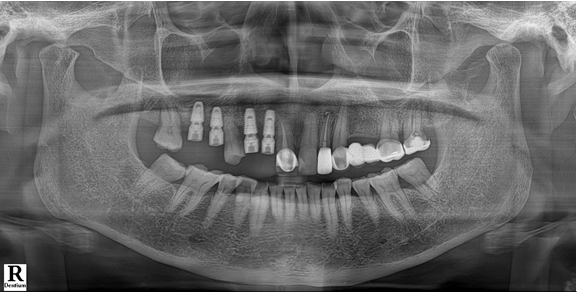

전치부는 지르코니아, 구치부는 보험임플란트 pfm 으로 제작 (70세 여자)

c.c: 앞니가 부러졌고, 오른쪽 어금니가 아파요.